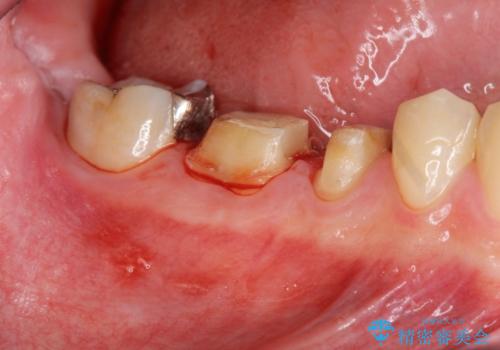

深い虫歯 セラミッククラウンの精度を高める歯周外科手術

- 歯ぐきからの排膿や出血、根尖病変の存在により他院で抜歯を提案され、歯を残す方はないかと当院に相談に見えました。

マイクロスコープを用いた根管治療を行ったのち、深い虫歯に起因する歯ぐきの腫れ・出血を改善すべく歯周外科を行いました。